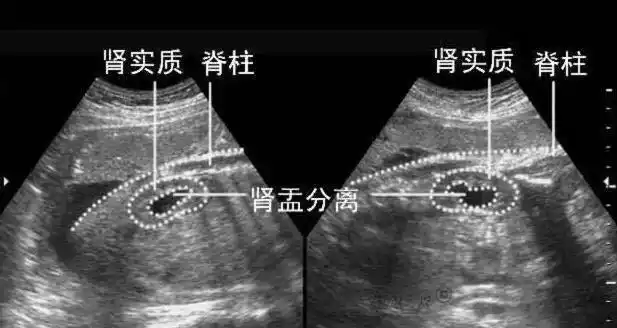

准妈妈们知道医生是如何通过b超单鉴定胎儿性别的吗get起来